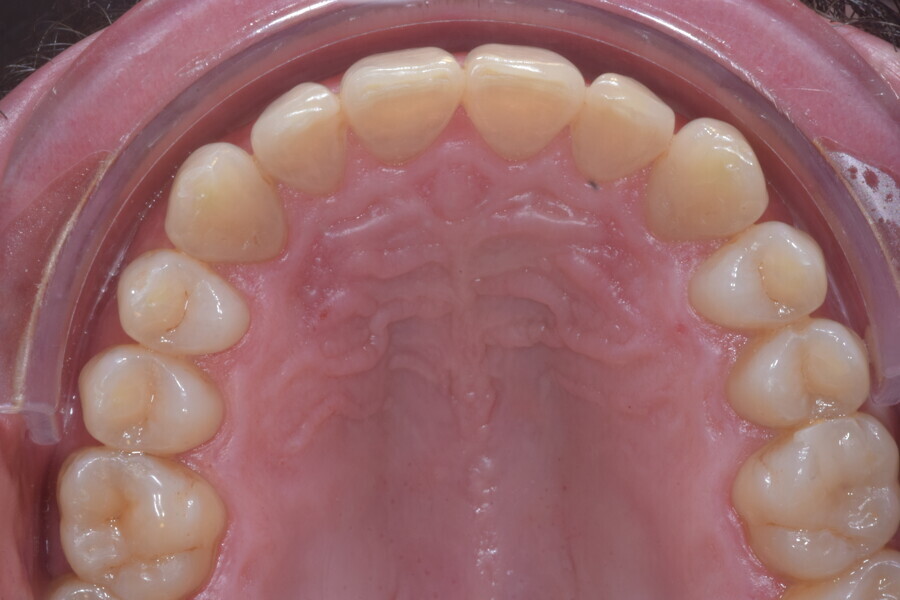

Le motif principal de consultation de ce patient âgé de 37 ans, était de rétablir l’alignement des dents antérieures sur les deux arcades. L’analyse faciale a indiqué une face courte avec un profil plat, mais une projection normale du menton (Figs. 9–12), et l’examen clinique a révélé une classe squelettique de type I (angle ANB = 0,89°) et une malocclusion de classe I avec supraclusion sévère (près de 100 %), une courbe de Spee très prononcée, un torque normal de l’incisive centrale supérieure (Ui-FH = 110°), un encombrement dentaire léger sur l’arcade maxillaire et modéré sur l’arcade mandibulaire (Figs. 13–18). Chez ce patient, les composantes de la supraclusion correspondaient à une dysmorphie squelettique grave correspondant à une hypodivergence (FMA = 14,24°), avec une inclinaison normale des incisives supérieures et inférieures et un angle goniaque réduit (110,46°). L’analyse du cliché céphalométrique indiquait une hauteur réduite de l’étage inférieur de la face associée à l’hypodivergence (Fig. 19). La seule option de traitement envisagée était un traitement orthodontique par aligneurs avec tous les éléments auxiliaires décrits (rampes d’occlusion, zones de pression, nivellement de la courbe de Spee dans les trois dimensions, élastiques de classe II et puissants contacts occlusaux) afin de corriger la supraclusion.

Le plan de traitement numérique (ClinCheck) avait prévu douze aligneurs pour l’arcade maxillaire et dix-sept pour l’arcade mandibulaire. Les objectifs du traitement visaient à combiner les mouvements verticaux d’extrusion des dents postérieures et les mouvements d’intrusion des dents antérieurs, au moyen de rampes d’occlusion, tout en utilisant des taquets d’extrusion pour assurer la désocclusion des dents postérieures et l’intrusion des dents antérieures inférieures, nécessaires au nivellement de l’arcade mandibulaire. La courbe de Spee a été nivelée et le profil plat ainsi que la position des lèvres ont été améliorés par une vestibulo-version des incisives supérieures et inférieures. Le plan avait prévu des élastiques de classe II pour faciliter la vestibulo-version des dents inférieures et les puissants contacts occlusaux postérieurs, avec une extrusion relative des dents postérieures. Une morphologie plus large de l’arcade et une intercuspidation idéale ont été obtenues par des mouvements de torque proches de 0° des dents latérales et postérieures supérieures. Aucune conception technique excessive n’avait été prévue dans le plan de traitement numérique. En raison de l’âge du patient, les aligneurs ont été changés tous les dix jours, dans le cadre d’un traitement d’une durée inférieure à six mois. À la fin de la première série d’aligneurs (Figs. 20–24), un nouveau plan de traitement numérique comportant cinq autres aligneurs a été conçu, en vue d’améliorer l’intercuspidation des molaires sans élastiques. La durée totale du traitement a donc été prolongée jusqu’à 7,5 mois puisque les aligneurs supplémentaires étaient changés toutes les semaines.

À la fin du traitement, on pouvait observer une relation de classe I des canines et des molaires, une légère augmentation de l’inclinaison des incisives supérieures (Ui-FH = 112°), une correction complète de l’inclinaison des incisives inférieures (IMPA = 97,09°) grâce à la vestibulo-version, et une légère amélioration de l’hypodivergence (SN-GoGn = 27°) résultant de l’extrusion relative des dents postérieures, et de l’utilisation d’élastiques de classe II — petite variation (1°) très intéressante compte tenu de l’âge du patient (Figs. 25–35). La ligne du sourire était harmonieuse et correspondait à une relation idéale entre les incisives supérieures et la lèvre inférieure. Le sourire avait été élargi grâce au contrôle du torque des segments latéraux et postérieurs.